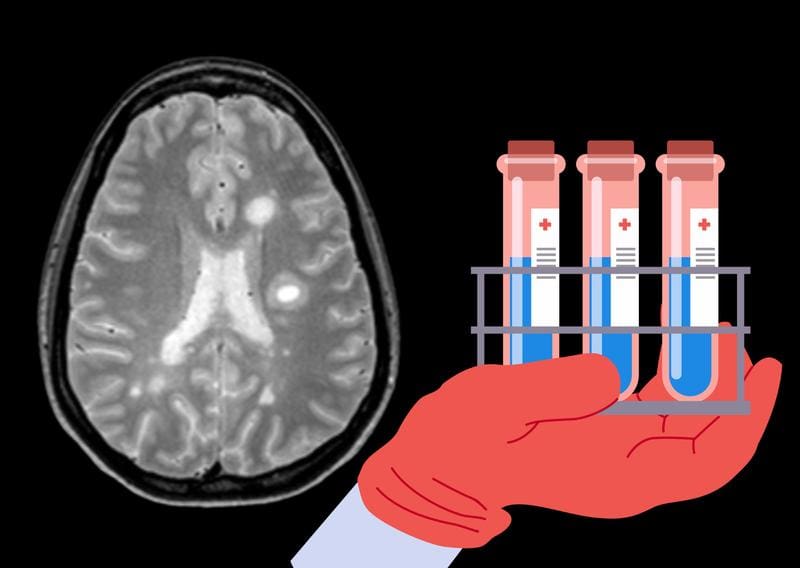

Researchers at the Max Planck Institute of Biochemistry in Martinsried and the Technical University of Munich have identified new diagnostic and prognostic markers for multiple sclerosis (MS). In a large-scale proteomic analysis, CSF samples from more than 5000 patients with various neurological diseases were examined using mass spectrometry.

About 1500 proteins could be quantified simultaneously per sample, and even up to 2100 proteins in an optimized method. The study uncovered systematic changes in the proteome of the cerebrospinal fluid (CSF) that allow for a more precise differentiation of multiple sclerosis from other inflammatory diseases of the central nervous system.

Particularly relevant is the discovery of a panel of 22 proteins that improves diagnosis in difficult cases – for example, in about ten percent of MS patients who lack classic evidence of oligoclonal bands. These markers exceed established parameters in differential diagnosis compared to similar inflammatory CNS diseases.

The method is based on further developments in mass spectrometry that allow high-throughput and in-depth protein analysis in body fluids. Non-specific neurological symptoms often complicate the early and reliable diagnosis of neurological diseases. The new findings could therefore contribute to accelerated and more reliable diagnostics and create the basis for individualized therapy decisions.